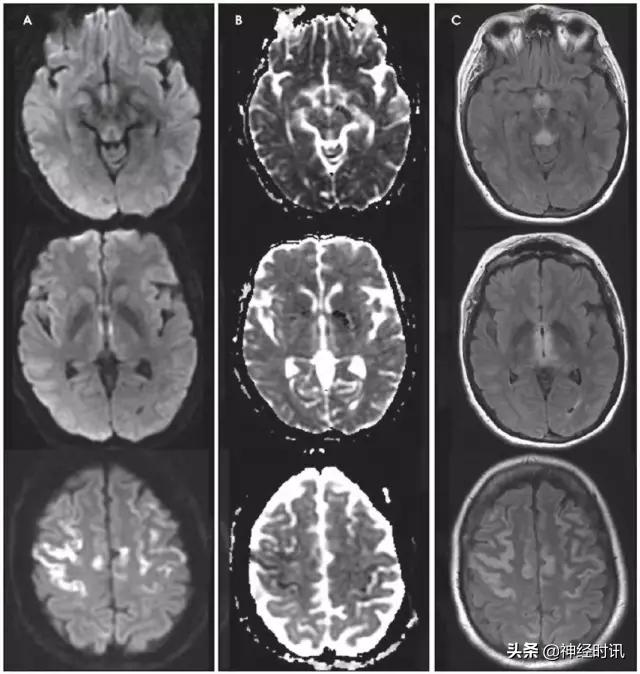

MELAS(线粒体脑病伴乳酸性酸中毒卒中样发作)

MELAS表现为恶心、呕吐、癫痫发作、肌无力和急性神经功能缺损,通常在40岁以前发病。MRI显示皮质和皮层下白质T2高信号、水肿和弥散受限。鉴别因素包括疾病进展不同阶段的多发病灶,急性病灶内同时存在弥散受限和增加,非血管性分布,以及好发于后部顶叶和枕叶(图6)。

图6 一例48岁男性,近期2次左侧PCA分布区梗死,伴神经功能缺损加重,新发认知功能障碍和意识障碍。最终诊断为MELAS,FLAIR显示左侧后顶颞针叶非血管性分布的皮层水肿(A:FLAIR),同时伴弥散受限和弥散增加(B:DWI;C:ADC)。